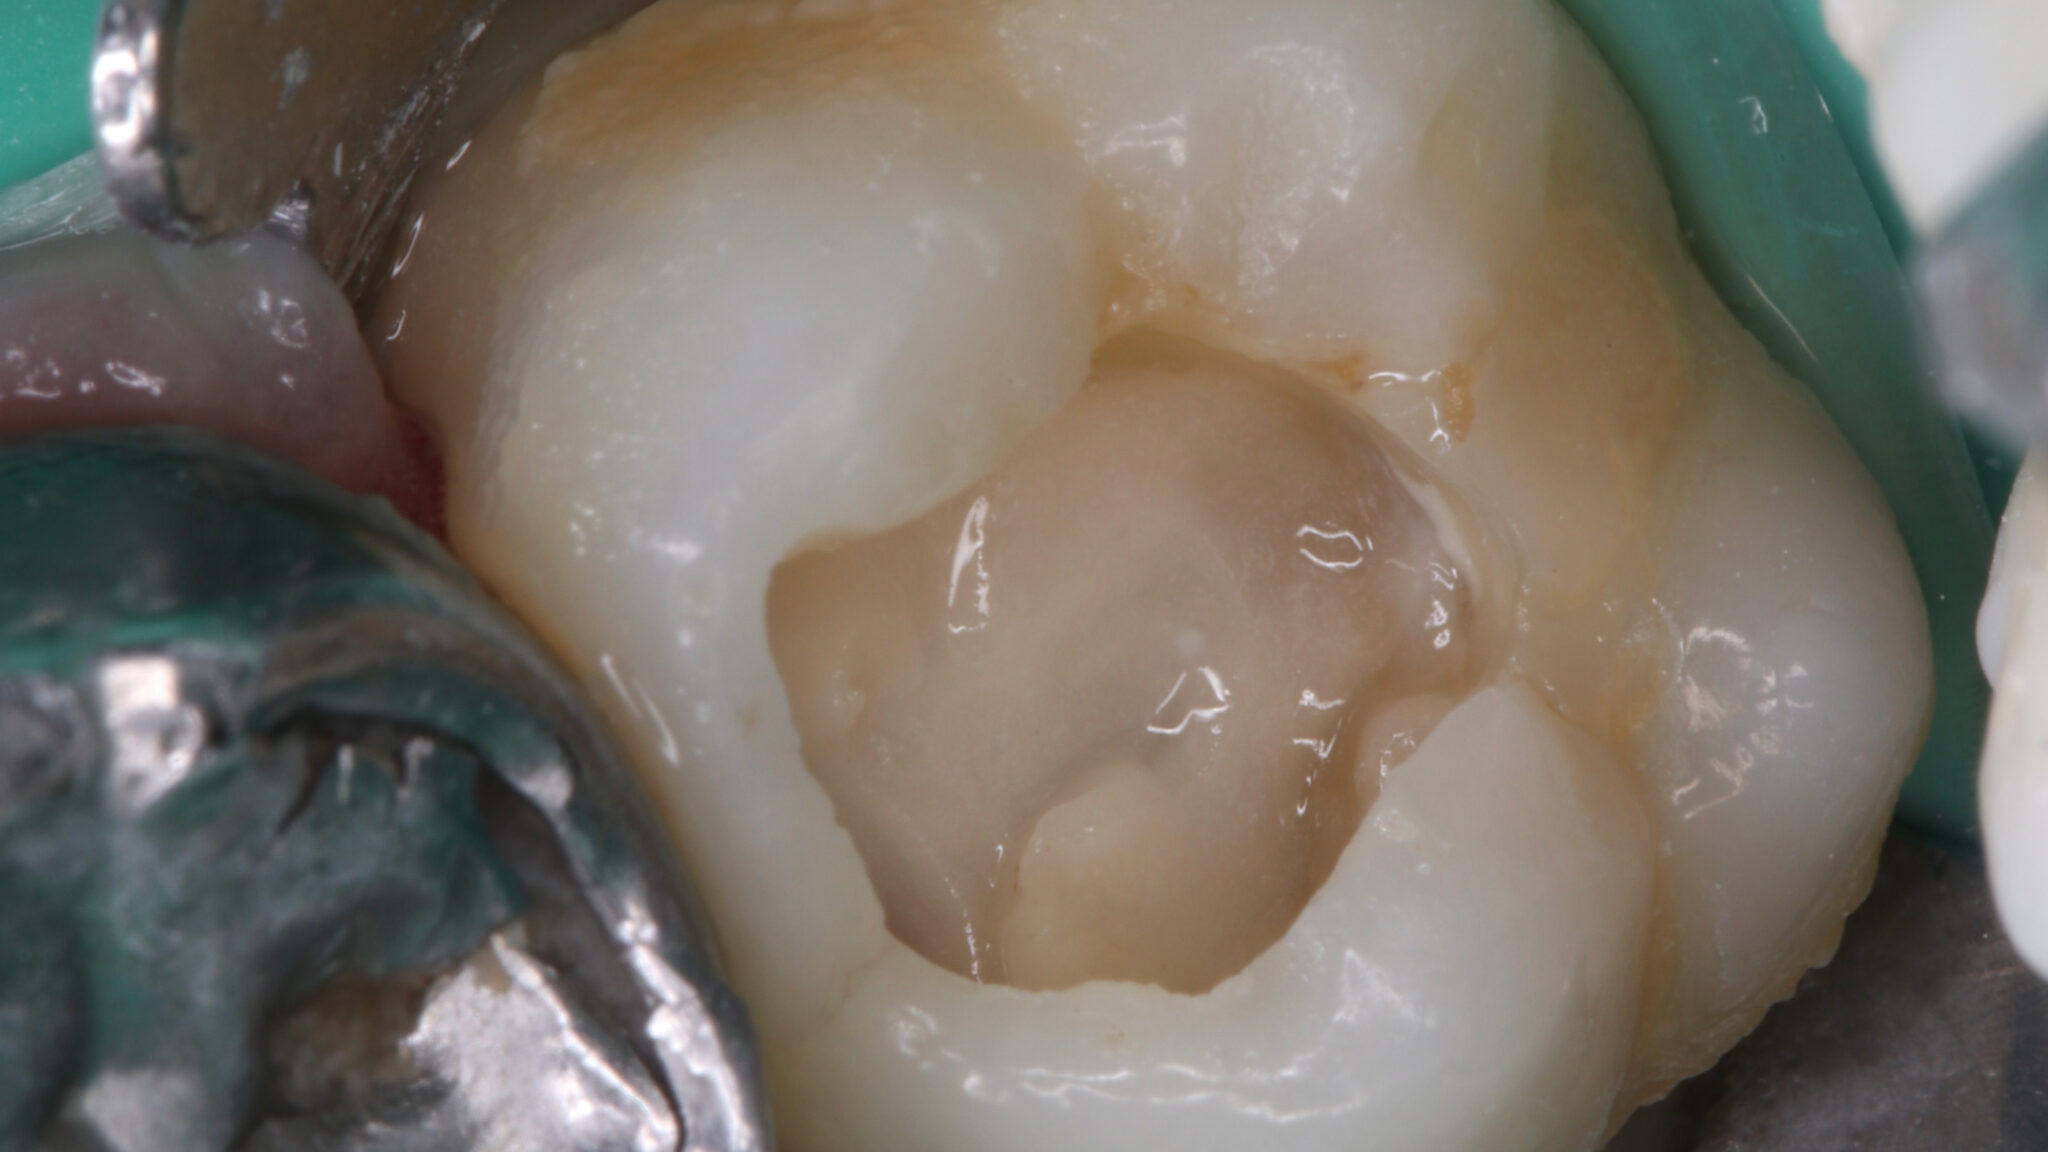

The Hall Technique – Teaching an Old Dog New Tricks

Step-by-step of the Clinical Hall Technique Procedure.

Background and Context Like many health fields, dentistry has been characterized throughout the years for innovating and improving upon existing interventions. Established and “classical” approaches, materials and techniques have often stood the test of time compared to more innovative and so-called “cutting-edge” technologies. In pediatric dentistry, this has proven to be true, especially when it … Read more